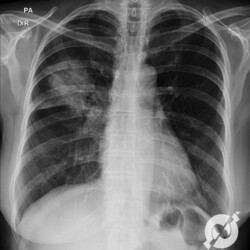

Os agentes etiológicos infecciosos são variados (bactérias, vírus, fungos, parasitas…), mas o que ocorre nos pulmões durante uma infecção por qualquer tipo de agente é a substituição do ar alveolar por secreção (pus, muco, eventualmente sangue ou necrose…) e com isso a manifestação radiográfica vai ser a mesma já que todas estas secreções apresentam a mesma densidade radiográfica: partes moles.

E o nome dado a esta alteração radiográfica que corresponde à substituição do ar alveolar por líquido é a consolidação alveolar.

Uma consolidação alveolar é, por definição, uma opacidade (imagem densa, branquinha) homogênea ou às vezes heterogênea (pela presença de calcificações ou cavidades), de limites mal definidos, exceto quando toca a pleura da parede ou das cissuras pulmonares. É um termo usado tanto em radiografia, como em tomografia computadorizada. Na tomografia, um outro termo é usado: vidro fosco, que é uma opacidade (branquinha mas não tanto como a consolidação), que borra o pulmão mas deixa ver os vasos de permeio (igual bigode de adolescente: dá pra ver todo o fundo).

Nós vamos mostrar aqui um pequeno apanhado de pneumonias de variados agentes, em diversos segmentos e lobos pulmonares, com extensões variadas. O objetivo é identificar o padrão radiológico de consolidação alveolar e não determinar o agente infeccioso, isso vai ser assunto para mais adiante. Aliás já antecipo que é fundamental saber localizar a lesão, porque alguns destes bichos gostam de determinados segmentos, alguns tumores também têm as suas preferências, então localização é fundamental. Se localização não fosse importante, um apartamento na beira do mar sairia o mesmo preço de um apartamento de frente pra BR-101, concordam?

Seguem alguns dos nossos casos de pneumonia para vocês treinarem os olhos e não se apavorarem nos plantões.